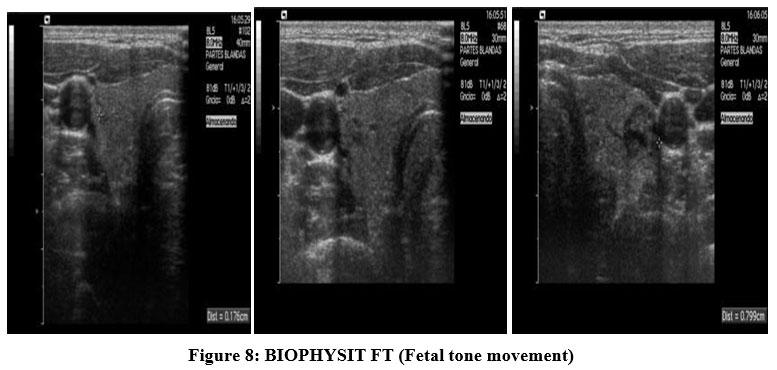

Which of the following are components of the biophysical profile (BPP)? Select all that apply

Explanation

Biophysical profile is a prenatal assessment tool that evaluates fetal well-being using real-time ultrasound and a non-stress test. It measures acute and chronic markers of hypoxia. Components scored include fetal breathing movements, body/limb movements, tone, amniotic fluid volume, and non-stress test. A normal score is 8–10. Normal amniotic fluid index (AFI) is 8–24 cm; normal single deepest pocket is 2–8 cm.

Rationale for correct answers

1. Fetal breathing movements are assessed by ultrasound; at least 1 episode of rhythmic breathing lasting ≥30 seconds in 30 minutes is normal.

3. Fetal movement is part of the BPP; ≥3 discrete body or limb movements within 30 minutes indicates normal activity.

4. Amniotic fluid volume reflects chronic uteroplacental function. A single vertical pocket ≥2 cm or AFI ≥5 cm is normal.

5. Non-stress test evaluates fetal heart rate accelerations with movement. Normal is ≥2 accelerations of ≥15 bpm lasting ≥15 seconds in 20 minutes.